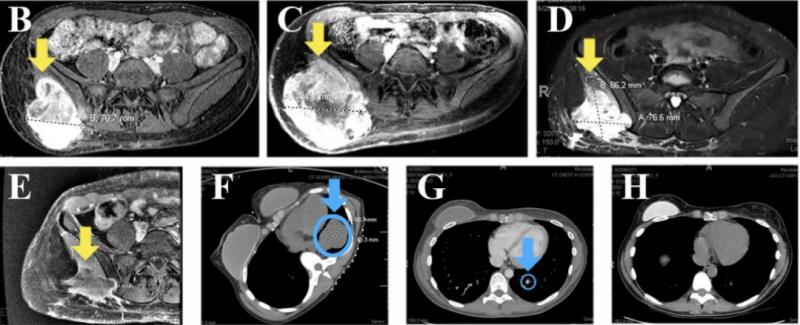

硫酸拉罗替尼胶囊疗效,16公分巨大肿瘤完全清除,肺转移消失,这款传奇抗癌药拉罗替尼临床试验招募正在进行中当检测出NTRK基因融合时,无论什么类型的癌症,无论肿瘤有多大,无论是否出现转移,拉罗替尼已经让全球各地的患者看到了肿瘤消退的“奇迹”。16公分巨大肿瘤完全清除,肺转移消失!传奇抗癌药为晚期癌症患者带来救赎2021年夏天,35岁的M女士因为右侧胯部疼痛肿胀